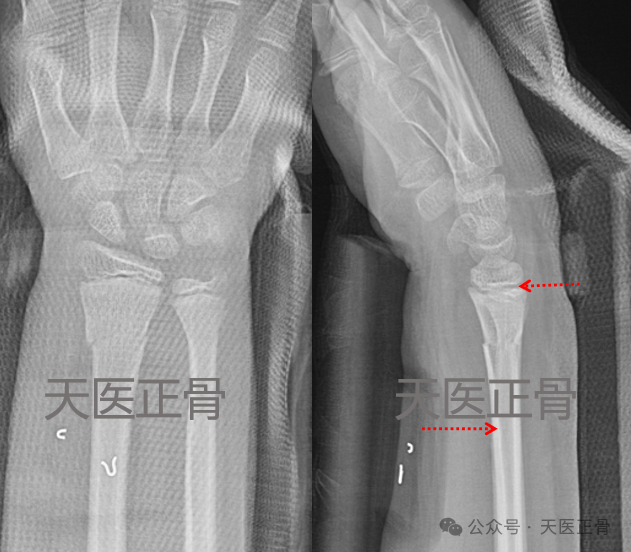

患儿男,10岁,摔伤致右桡骨远端骨折,于伤后1小时当地行闭合复位石膏固定,1周复查发现骨折成角加剧,为求进一步治疗~,外埠来津求医。

1周后复查,侧位成角加剧,约20°